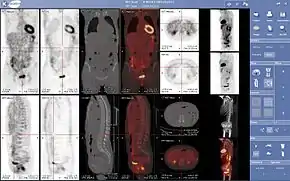

Normal whole body PET/CT scan with FDG-18. The whole body PET/CT scan is commonly used in the detection, staging and follow-up of various cancers.

Abnormal whole body PET/CT scan with multiple metastases from a cancer. The whole body PET/CT scan has become an important tool in the evaluation of cancer.